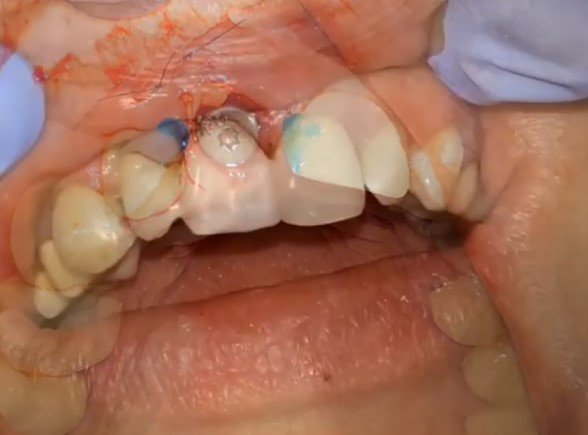

Фронтальные зубы как никогда важны для пациента! Конечно работа с передними зубами сложна и кропотлива! Требует особой тактики ведения. @dr.logvinov...